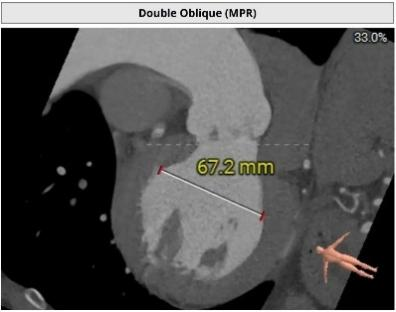

主动脉根部评估:

瓣环周长103.7mm,周长径33mm

LVOT周长103.1mm,周长径32.8mm

STJ 周长径45.3mm

升主动脉周长径48.1mm

SOV 43.4mm*44.5mm*40.2mm

瓣环水平夹角66°